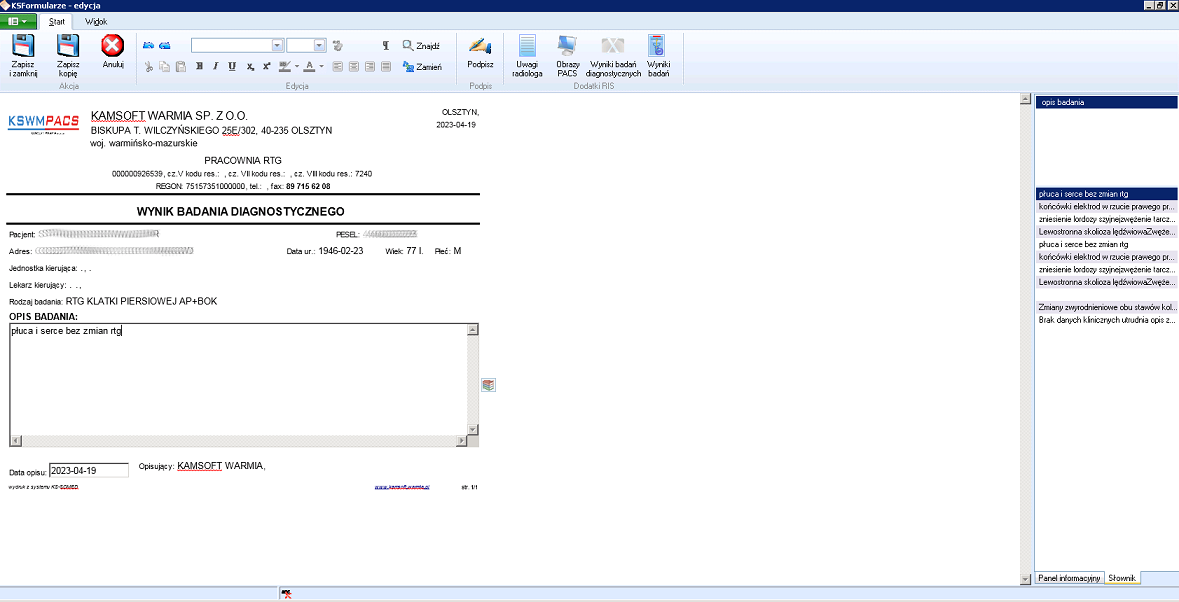

Rozwiązanie zawiera wszystkie elementy informatyczne umożliwiające obieg informacji medycznej, pozwala na tworzenie i udostępnianie elektronicznej dokumentacji medycznej EDM. Integracja pomiędzy systemem medycznym i systemem PACS umożliwia przekazywanie zleceń na badania i odbieranie wyników oraz rozliczenia usług. Opcjonalnie system umożliwia wysyłanie badań do zdalnego opisu.

- Przeglądarka diagnostyczna DICOM do opisu badań

- Przeglądarka DICOM do prezentacji wyniku badania lekarzowi

Oferujemy dla naszych Klientów dostawę i uruchomienie rozwiązania informatycznego, które umożliwia obieg informacji medycznej pomiędzy gabinetem lekarskim i pracownią diagnostyki obrazowej. W efekcie nie tylko usprawnia się proces leczenia pacjenta, ale również rozliczenie usług diagnostyki obrazowej. Dodatkowo system umożliwia raportowanie zdarzeń medycznych z diagnostyki obrazowej do systemu P1.